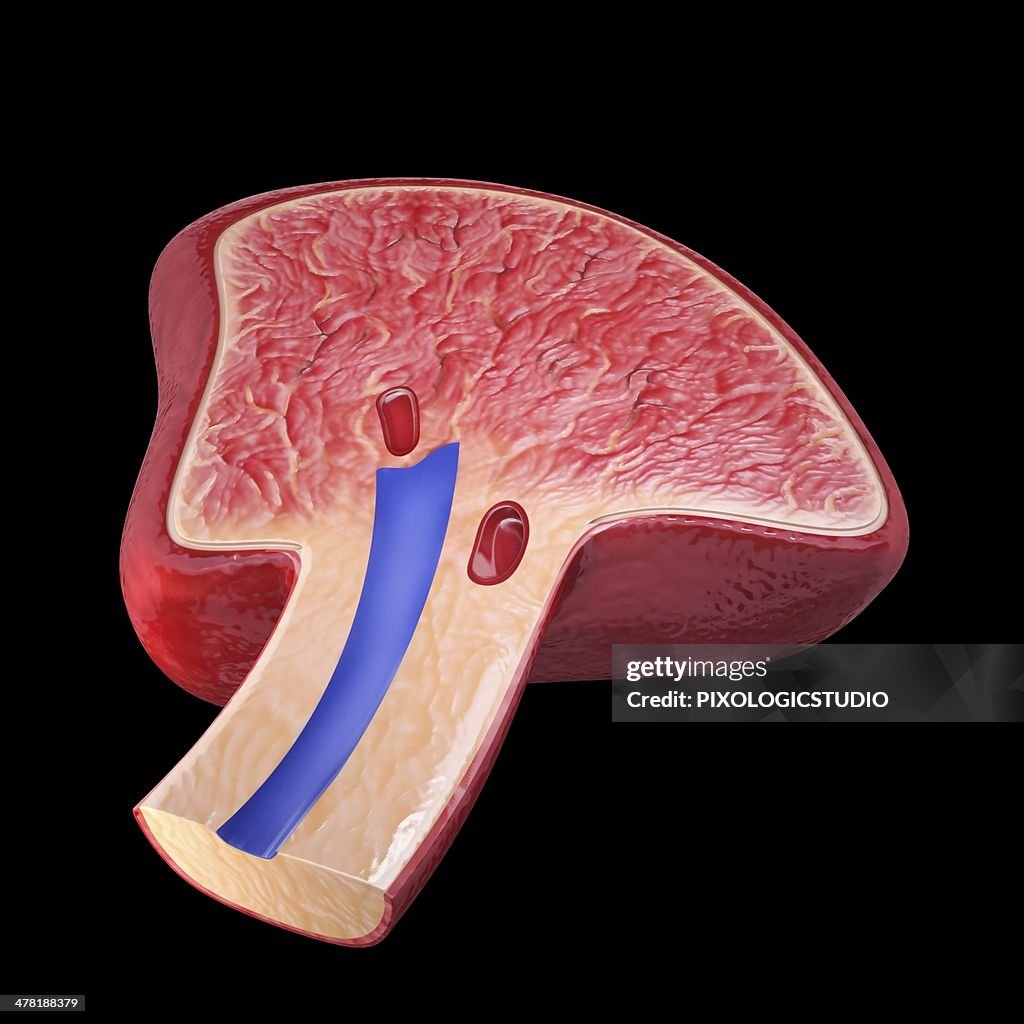

Human spleen, artwork - Stock-Grafiken

Human spleen, cut-away computer artwork.

- Anatomie,

- Arterie,

- Biologie,

- Biomedizinische Illustration,

- Blutgefäß,

- Dreidimensional,

- Immunsystem,

- Inneres Organ eines Menschen,

- Milz,

- Milzarterie,

- Querschnitt,

- Schnittzeichnung,